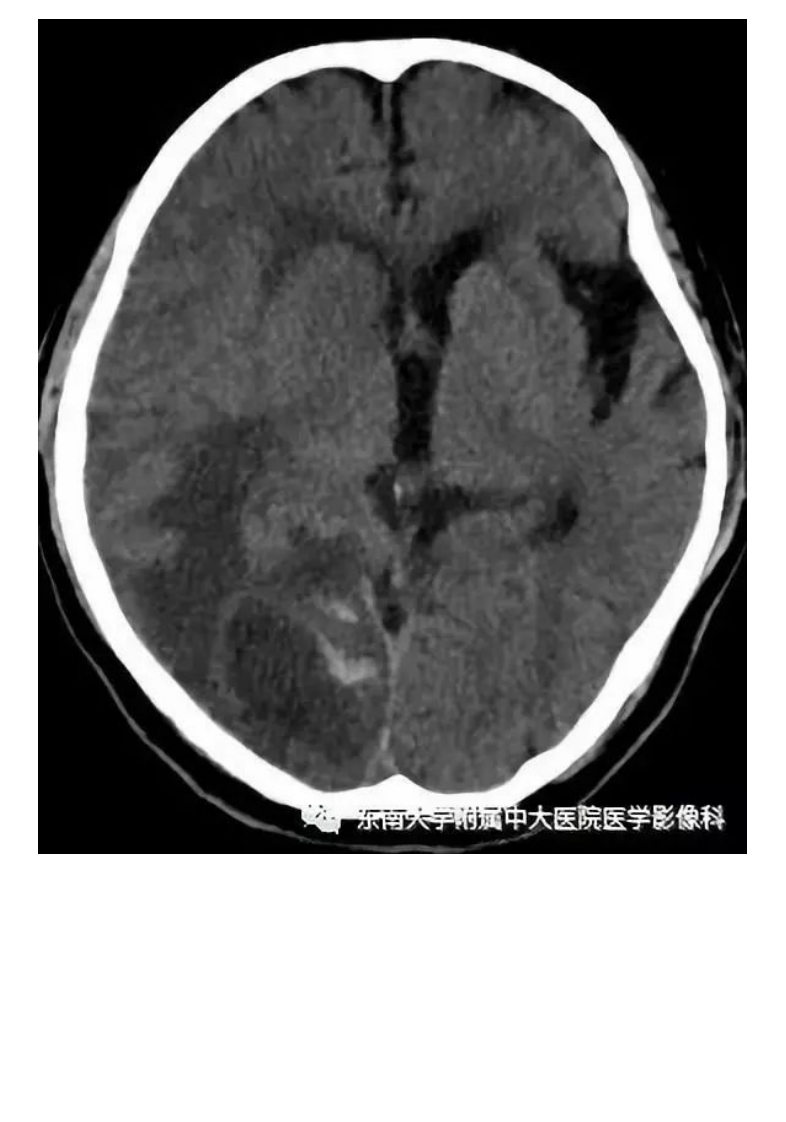

20190909_2【晨读结果公布】2019.09.09神经系统疾病.pdf

20201129_1【中大放射住培系列讲座】急性出血性脑血管病影像指导规范.pdf